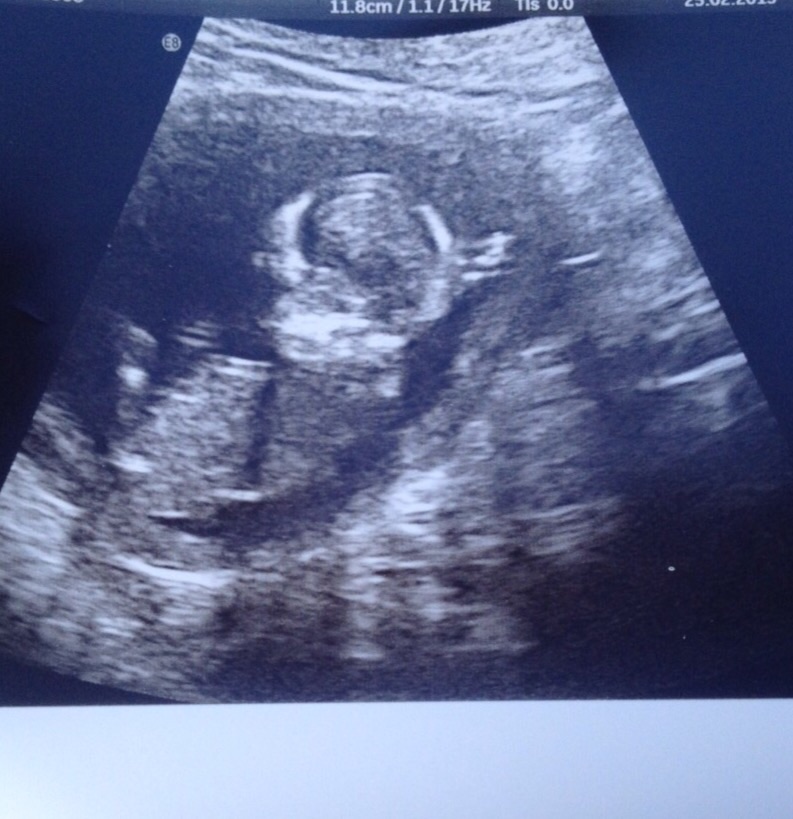

Nub guesses for a friend please

hi could you's guess my friends pic please thank you xxx

No nub.